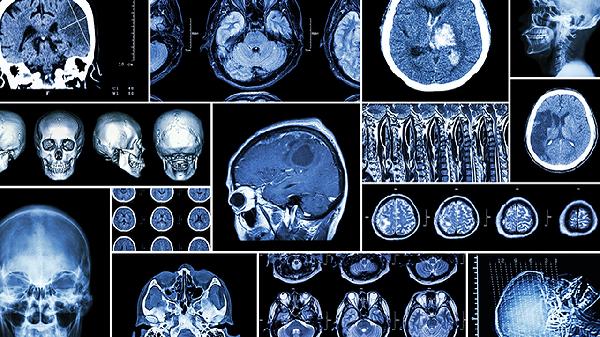

每3-6个月进行头颅CT或MRI检查评估血管状况,每年完成颈动脉超声和心电图筛查。监测血糖、血脂、同型半胱氨酸等指标,及时发现血管病变风险。康复期患者需定期评估肢体功能与语言能力,必要时进行康复训练。